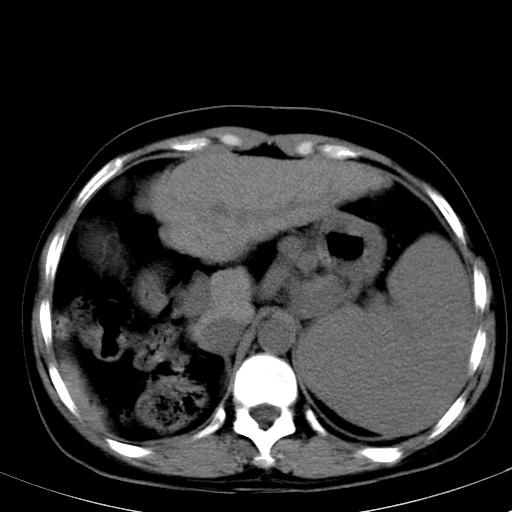

肝硬化、门脉高压、脾大。再障+肝硬化促成巨脾。

左肝大/右肝小,脾大,考虑肝硬化门脉高压,脾大。  不知是否有血吸虫感染病史

肝硬化,门脉高压,脾大。

肝硬化,门脉高压,脾大。支持大家。

肝叶比例失调,肝左叶明显增大,包膜欠规整,脾大,支持考虑肝硬化、门脉高压、脾大。